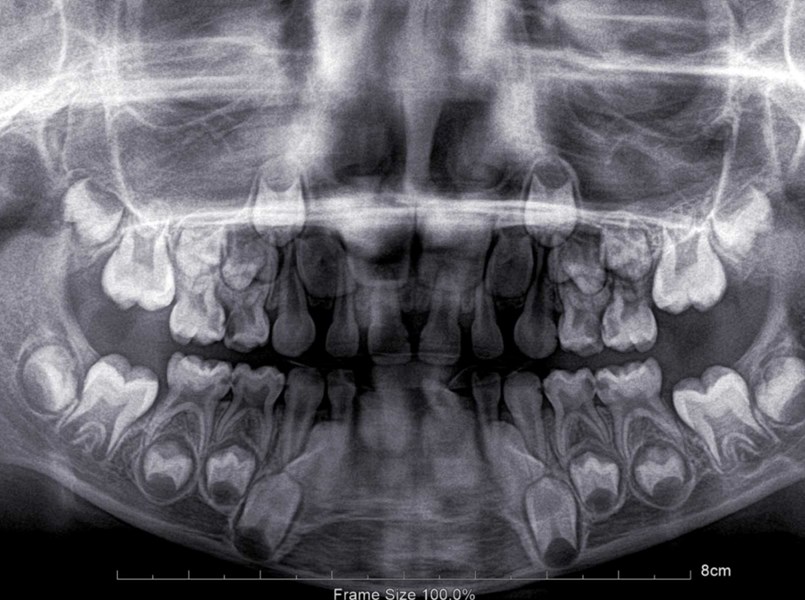

I denti da latte sono i primi denti che compaiono nei bambini, di solito tra il sesto e il dodicesimo mese di vita. Sono fondamentali per la corretta masticazione, il normale sviluppo delle mascelle e il mantenimento dello spazio per i denti permanenti. In totale quanti sono i denti da latte? Sono 20.

I denti nei neonati di solito iniziano a spuntare tra il sesto e il dodicesimo mese di vita. Tuttavia, in alcuni bambini l’eruzione può avvenire già a quattro mesi, mentre in altri il primo dentino compare solo dopo il primo compleanno.

Intorno ai sei anni i denti da latte iniziano a cadere, anche se il momento preciso varia da bambino a bambino.

Il processo di caduta comincia con gli incisivi inferiori, seguiti da quelli superiori. I molari cadono per ultimi, di solito tra i dieci e i dodici anni.

In questo periodo iniziano a erompere i denti permanenti che sostituiscono quelli da latte. Il primo molare permanente, chiamato “sesto”, erompe intorno ai sei anni dietro l’ultimo dente da latte.

Tra i 7 e gli 8 anni è consigliato portare il bambino a una visita ortodontica, per valutare la necessità di un trattamento precoce e assicurare il corretto sviluppo dei denti e delle mascelle. In questa fase può essere utile anche uno schema caduta denti da latte per seguire l’ordine naturale di eruzione e sostituzione.

Di solito compaiono per primi gli incisivi inferiori e, entro i tre anni, la maggior parte dei bambini ha tutti i 20 denti da latte.